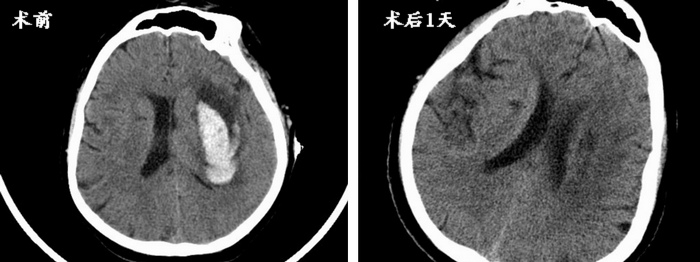

突如其来的疾病对张先生和他的家庭来说是巨大的打击。为了让患者重获健康,张洪兵主任迅速组织神经外科团队针对患者病情进行分析,团队讨论结果认为应清除血肿,缓解其对神经纤维束的压迫,促进患者肢体功能康复。但是该患者颅内出血位于大脑深部,开颅清除血肿势必会给患者带来巨大创伤,而采用立体定向技术对大脑深部血肿进行穿刺引流,将会达到微创治疗和快速康复的目的,使患者在最小的创伤下更快的恢复肢体功能。在医学影像科的大力协助下,神经外科团队为患者完善了术前影像评估及定位,将所获得的影像数据应用Leksel立体定向系统进行精确计算,最终设计出了恰当的穿刺引流路径及靶点,逐步实施穿刺步骤,成功完成了血肿引流。术后第一日,张先生的肢体功能就显著改善,复查头部CT提示血肿引出完全。目前张先生经过肢体功能的康复治疗右侧肢体已可做简单的活动。